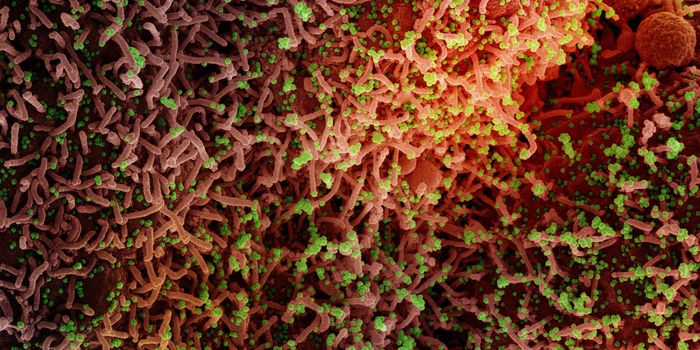

JUL 15, 2022Health & MedicineVariants of SARS-CoV-2, the virus that causes COVID-19, have been continuously emerging since the start of the pandemic. ...